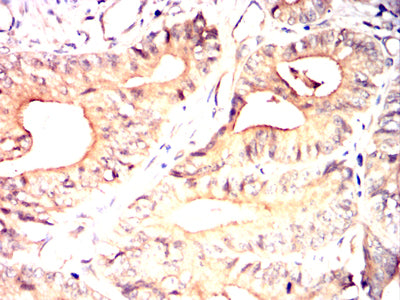

- Immunohistochemical analysis of paraffin-embedded human colon cancer tissues using NOTCH4 mouse mAb with DAB staining.